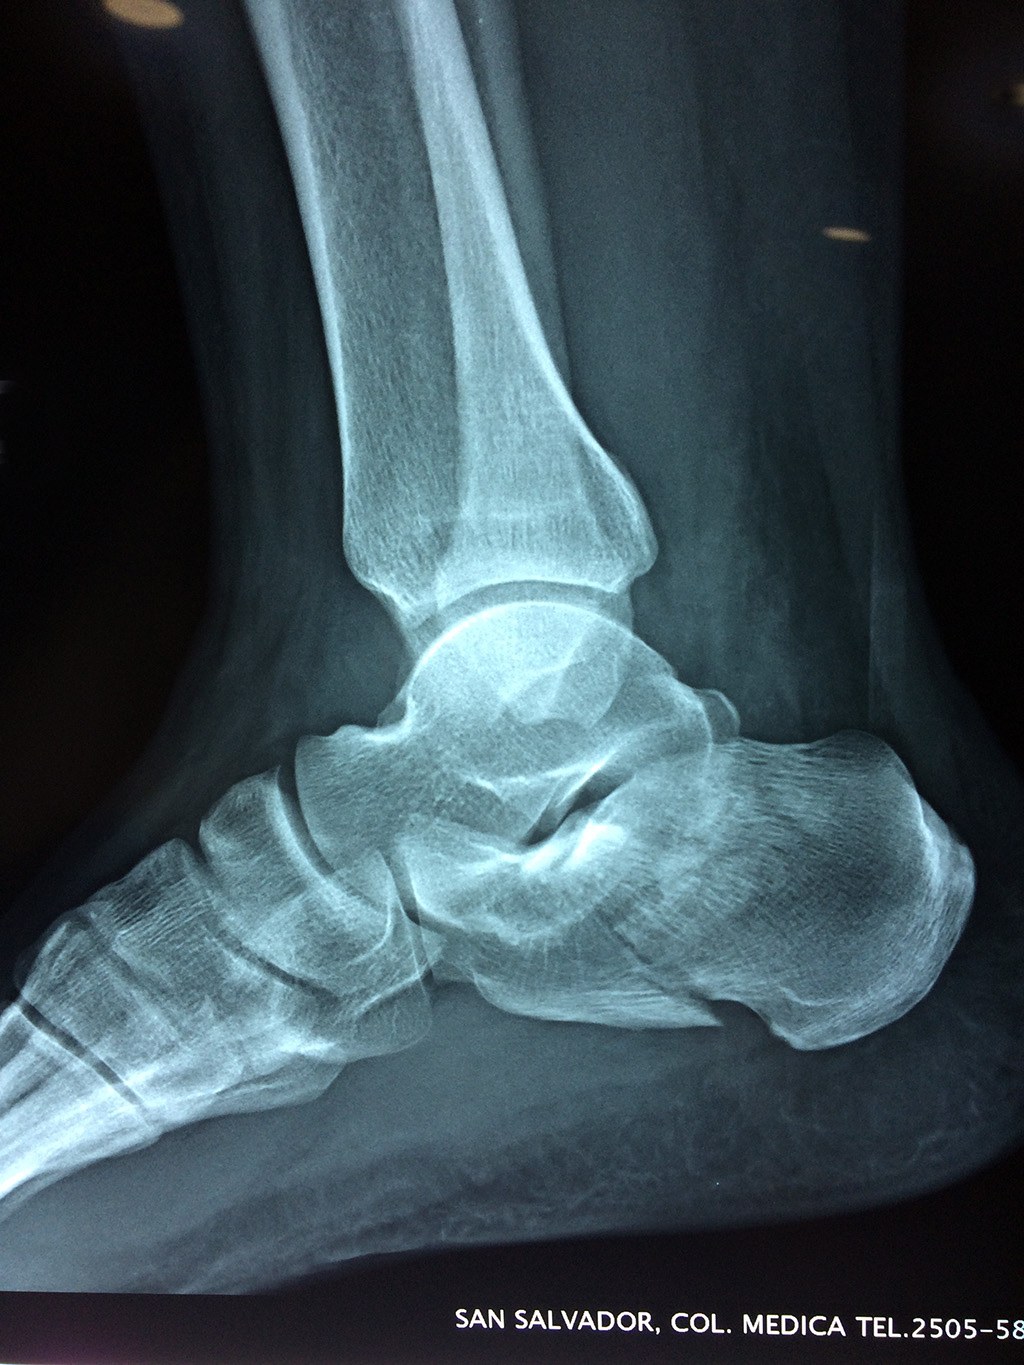

El calcáneo (del latín Os calcis) es un hueso del pie (tarso), corto, asimétrico, de forma cúbica irregular, con seis caras: superior e inferior, laterales y anterior y posterior, de las cuales dos son más o menos articulares.

Este hueso constituye el talón del pie. Se encuentra en la parte inferior de la primera fila del tarso. Se articula con el astrágalo por arriba y con el cuboides por delante. Constituye el primer punto de apoyo del pie durante la marcha, situándose en una de las zonas peor irrigadas del cuerpo y protegido plantarmente por la almohadilla plantar de tejido adiposo, con función amortiguadora.

En su cara posterior recibe la inserción del tendón más plantar, implicada en diversas enfermedades como la fascitis o el espolón calcáneo. La posición del calcáneo en relación al astrágalo (articulación subastragalina) y al suelo determinan la posición de retropié en varo, en valgo o neutra.